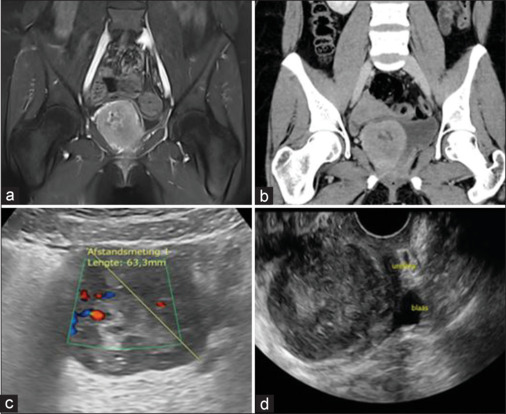

Perivascular epithelioid cell neoplasm (PEComa) is a rare mesenchymal tumor composed of histologically and immunohistochemically distinctive perivascular epithelioid cells. They can arise in various localizations such as the bladder. A total of 36 case reports regarding bladder PEComa have been described in the literature. Eleven reviews regarding this tumor have been published in literature so far primarily focusing on anatomic pathology. Through these reviews, it is known that in bladder PEComa, the melanocytic marker Human Melanoma Black-45 is expressed in 100% of cases whereas variable expression can be seen in multiple other melanocytic and myoid markers such as smooth muscle actin, Melan-A, CD117, S100, CD31, and CD34. Since current reviews mainly emphasize anatomic pathology, we perform a review focusing on the clinical aspects of PEComa at the level of the clinician. A manual electronic search of the PubMed/Medline and Web of Science Core Collection databases was conducted. Search was done on (perivascular epithelioid cell neoplasms [MeSH terms]) AND (Bladder). All case reports and reviews were encompassed until March 15, 2023, to identify studies that assessed bladder PEComa. The age of presentation is relatively low with a median age of 37 years. There is a female predominance with a female/male ratio of 1.5. The tumor shows no preference in anatomical localization within the bladder. Even involvement of the bladder neck, proximal urethra, and distal ureter has been described. The clinical presentation consists in the majority of patients of symptoms related to the urinary tract such as hematuria, dysuria, passage of urine sediment, frequency, and urgency. Other symptoms include abdominal discomfort and dysmenorrhea. In clinical examination, an abdominal mass can be found based on the size and location of the tumor. Further examination usually encompasses cystoscopy due to the hematuria and radiological investigations such as ultrasound (US), computed tomography, and magnetic resonance imaging. These radiological investigations reveal a heterogeneous solid mass with clear borders. In our center, we performed a transvaginal US additionally in a patient with bladder PEComa, which was the only investigation in our patient that concluded the mass was located in the Retzius space. For treatment, transurethral resection of the bladder tumor and partial cystectomy were both described in equal numbers. The choice of treatment depends on the localization and size of the tumor. Follow-up consists of imaging, but clear guidelines on this matter are lacking. Bladder PEComa is a rare condition and usually presents itself with nonspecific symptoms. Radiological investigations will reveal the tumor, but the final diagnosis is based on cytological and immunohistochemical features. Since bladder PEComa is an entity with uncertain malignant potential, it is important to include this entity in the differential diagnosis when a patient presents with lower abdominal discomfort and lower urinary tract symptoms in combination with a mass in the pelvic region.